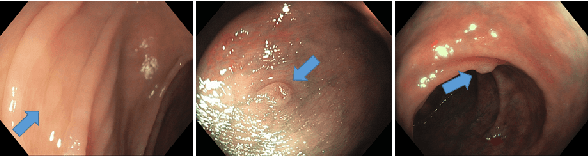

Abstract:Colorectal cancer, largely arising from precursor lesions called polyps, remains one of the leading causes of cancer-related death worldwide. Current clinical standards require the resection and histopathological analysis of polyps due to test accuracy and sensitivity of optical biopsy methods falling substantially below recommended levels. In this study, we design a novel capsule network architecture (D-Caps) to improve the viability of optical biopsy of colorectal polyps. Our proposed method introduces several technical novelties including a novel capsule architecture with a capsule-average pooling (CAP) method to improve efficiency in large-scale image classification. We demonstrate improved results over the previous state-of-the-art convolutional neural network (CNN) approach by as much as 43%. This work provides an important benchmark on the new Mayo Polyp dataset, a significantly more challenging and larger dataset than previous polyp studies, with results stratified across all available categories, imaging devices and modalities, and focus modes to promote future direction into AI-driven colorectal cancer screening systems. Code is publicly available at https://github.com/lalonderodney/D-Caps .